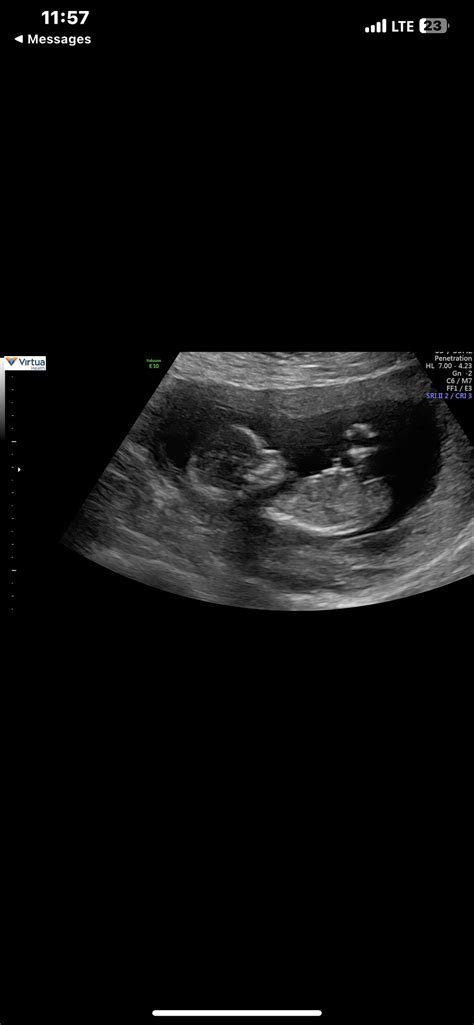

14 Week Ultrasound

Pregnancy is an exciting journey filled with milestones, and one of the most anticipated moments is the 14 week ultrasound. This scan is a crucial part of prenatal care, providing valuable insights into the baby's development and the mother's health. Understanding what to expect during a 14 week ultrasound can help alleviate anxiety and prepare you for this important appointment.

During the 14 week ultrasound, you will lie on an examination table with your abdomen exposed. The technician will apply a gel to your belly and use a transducer to capture images of your baby. The procedure is painless and usually takes about 20-30 minutes.